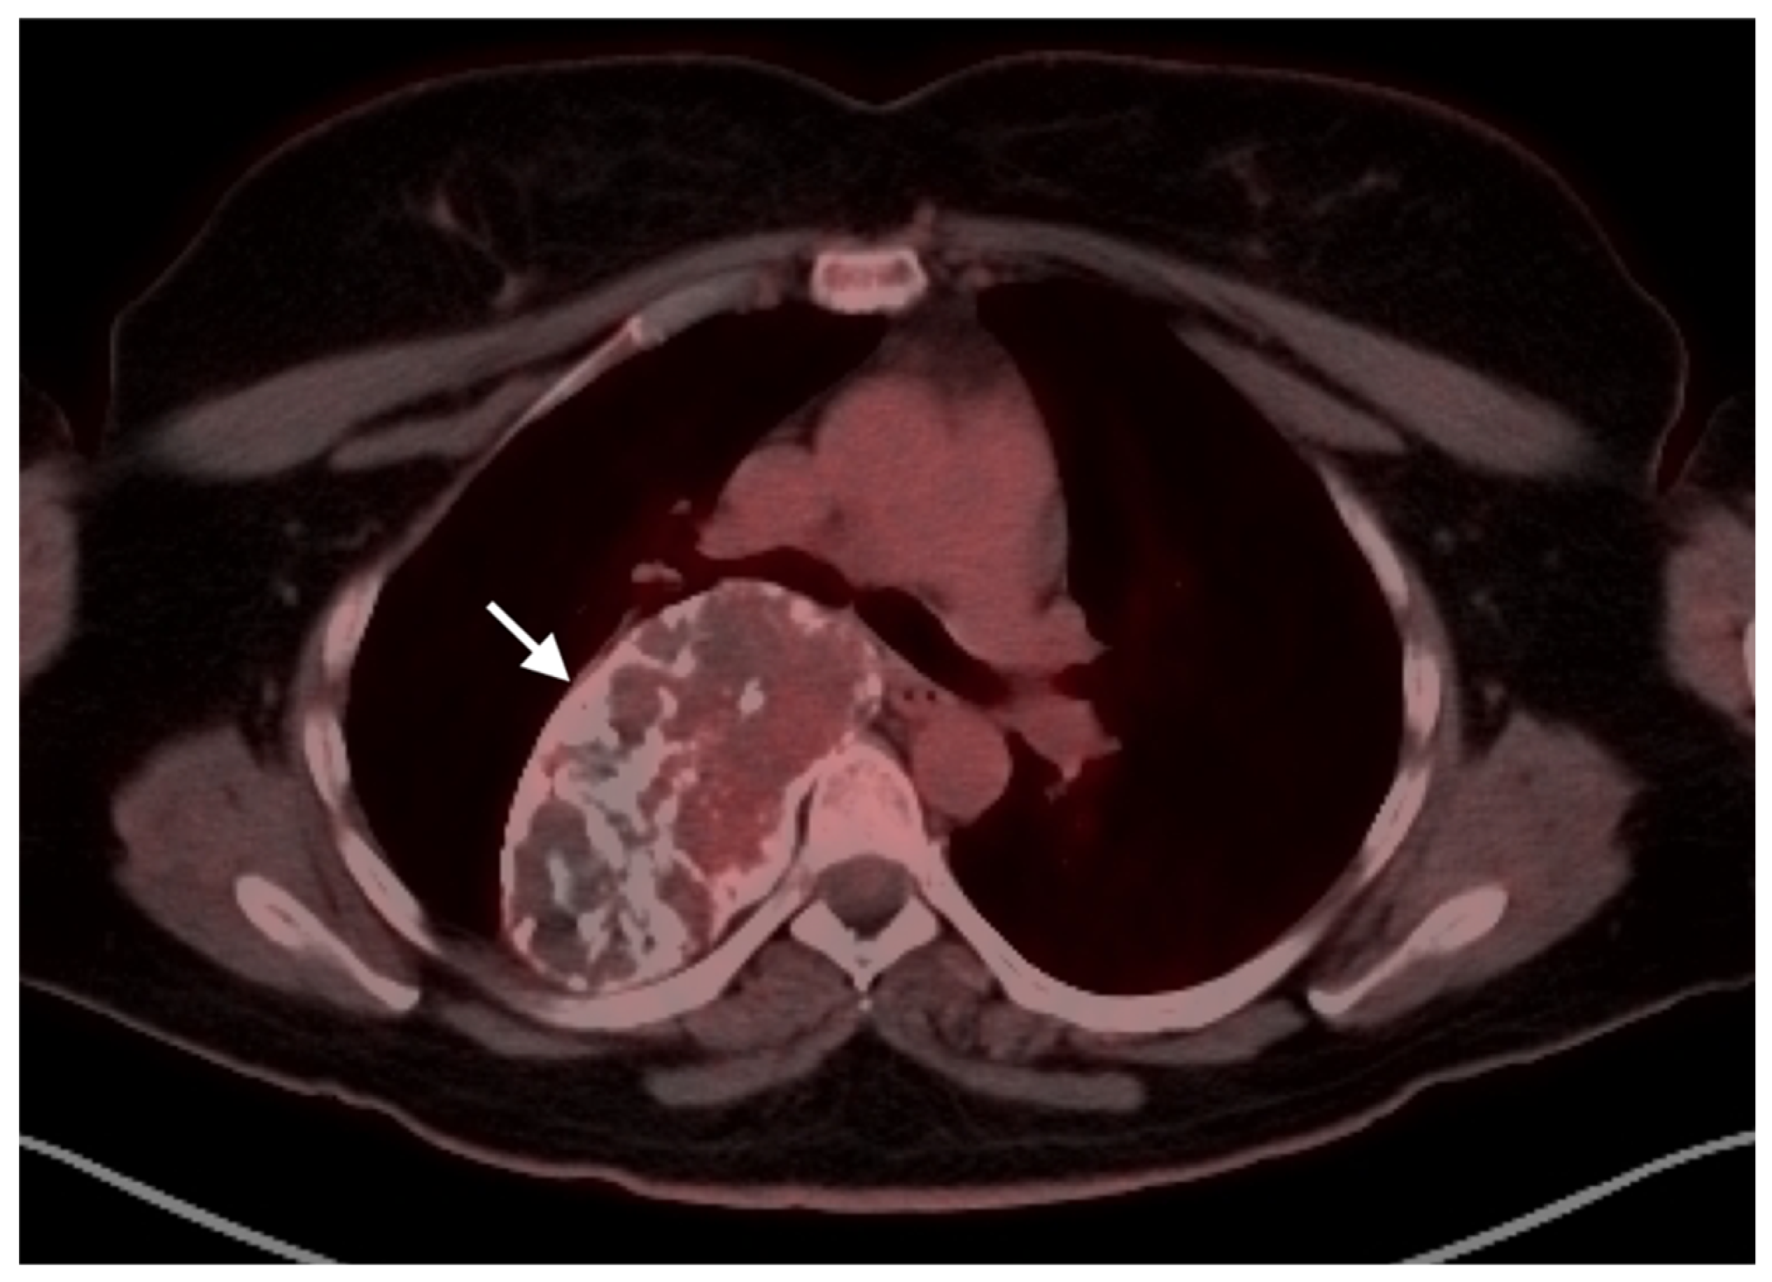

- Gao, Y.-J.; Yang, Z.; Yu, J.-Y.; Li, N.; Wang, X.-J.; Zhou, N.-N. Potential application value of PET/computed tomography in retroperitoneal leiomyosarcoma and a literature review. Nucl. Med. Commun. 2021, 42, 800–810. [Google Scholar] [CrossRef]

- Subramaniam, S.; Callahan, J.; Bressel, M.; Hofman, M.S.; Mitchell, C.; Hendry, S.; Vissers, F.L.; Van der Hiel, B.; Patel, D.; Van Houdt, W.J.; et al. The role of 18 F-FDG PET/CT in retroperitoneal sarcomas—A multicenter retrospective study. J. Surg. Oncol. 2021, 123, 1081–1087. [Google Scholar] [CrossRef]